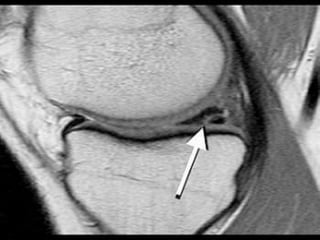

Torn meniscus on MRI (left) and during arthroscopy (right)

Torn meniscus onMRI (left) and during arthroscopy (right)

• #23 Normally the medal and lateral menisci appear as low signal bow-tie-shaped structures between the femoral condyles and tibial plateauxThe absent bow tie sign represents the loss of the normal appearance of the menisci on parasagittal MRI images, and is suggestive of meniscal injury.

• #27 The double PCL sign appears on sagittal MRI images of the knee when there is a bucket-handle tear of the meniscus